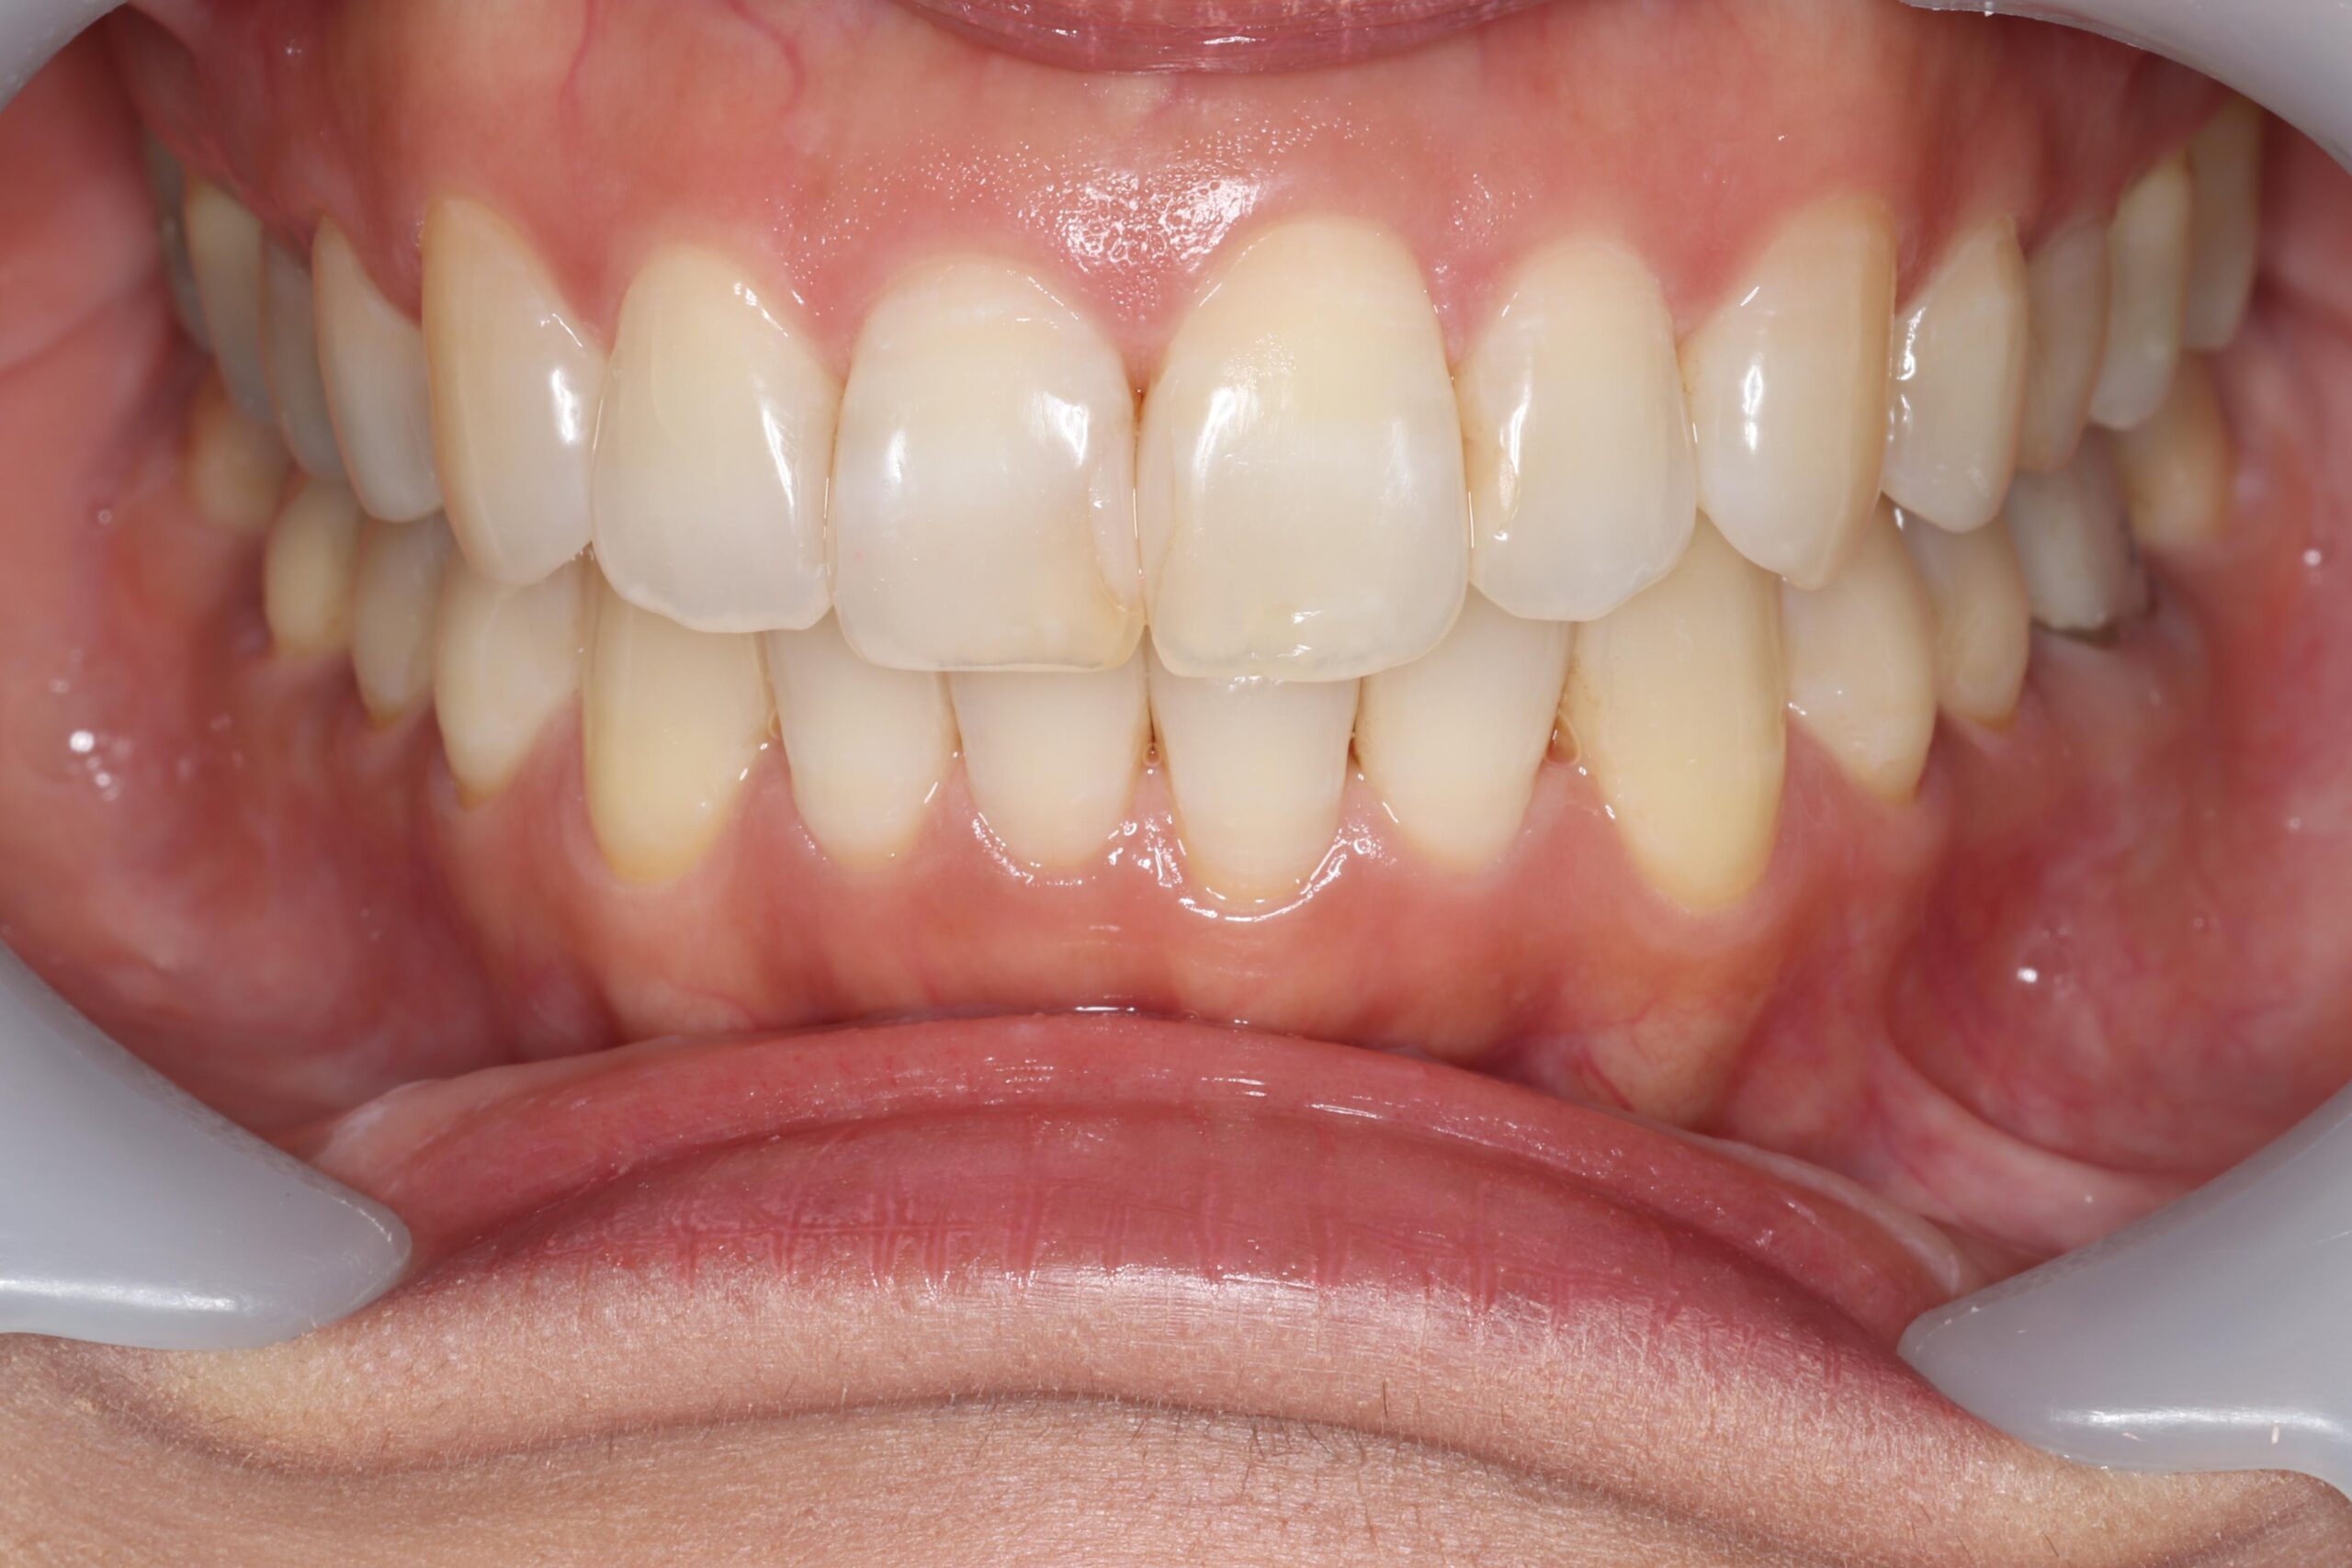

矯正治療の目的の多くは、歯並びを綺麗にすることだと思いますが、口元の印象が変わるだけで、相手に与える印象は大きく変わると言われています。矯正治療前は「いつも口元を隠して笑っていた」とおっしゃっていた患者様が、治療後に満面の笑みで「自信が持てるようになった」とお話しくださります。

歯並びがガタガタしていたり、重なっていたりすると、どうしても磨き残しによる虫歯や歯周病のリスクが高まります。綺麗な歯並びは、歯磨きがしやすくなり虫歯や歯周病予防にも繋がります。